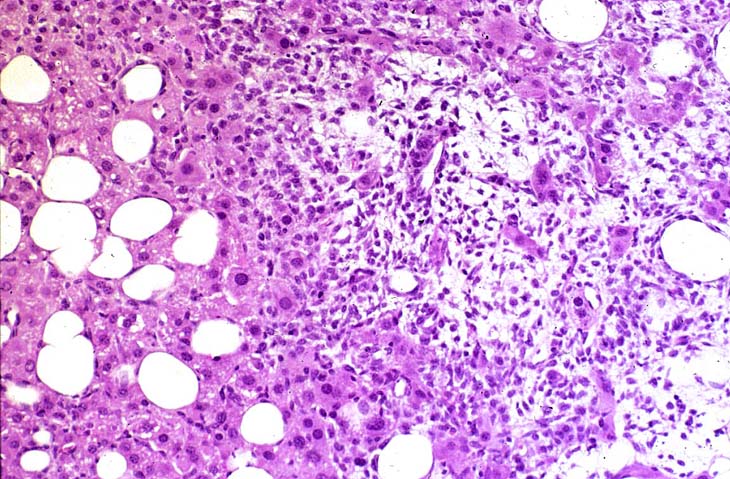

A relative discrete Ito cell tumor is present within this hepatic lobe; a higher magnification shows proliferation of stellate cells within the hepatic sinusoidal spaces.